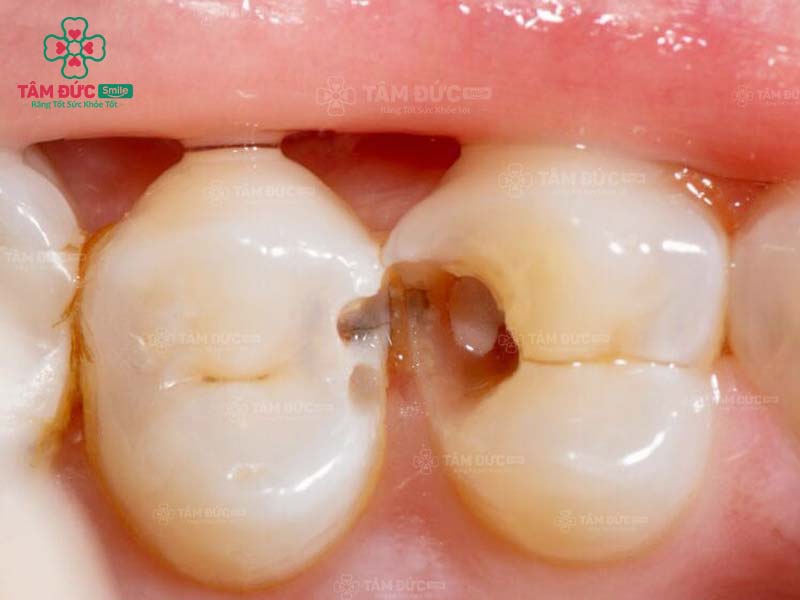

1.1. Răng bị sâu

Khi răng bị sâu, trên thân răng xuất hiện các lỗ nhỏ li ti. Đây chính là vị trí trú ngụ của hàng nghìn loại vi khuẩn. Cùng với thói quen chăm sóc răng miệng không tốt, ăn thực phẩm chứa nhiều đường, lỗ sâu răng sẽ lớn dần và gây đau nghiêm trọng. Nguy hiểm nhất chính là nhiễm trùng và mất răng vĩnh viễn.

Trám răng giúp lấp đầy các lỗ hổng trên thân răng. Nhờ đó, các triệu chứng khó chịu, biến chứng do răng sâu được loại bỏ triệt để. Thẩm mỹ của chiếc răng bị sâu nói riêng và cả hàm răng nói chung đều được phục hồi.

răng sâu cần trám răng

răng hàm bị sâu

răng nanh bị sâu cần trám